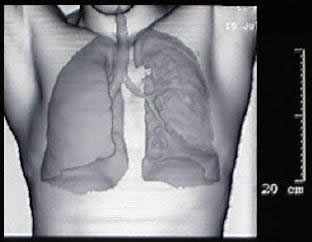

un paciente joven, con un gran tumor del mediastino anterosuperior de rápido

crecimiento, correlacionando su tamaño entre la radiografía

del tórax y los hallazgos tomográficos realizado 15 días

después, y las condiciones físicas al momento de su intervención,

con gran dificultad respiratoria.